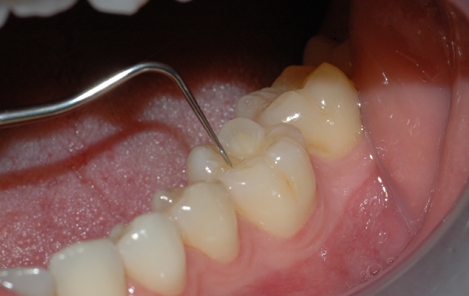

Tannlegen undersøker hver enkelt tann etter hull og skader

Tannkjøttet og tennenes benfeste blir vurdert